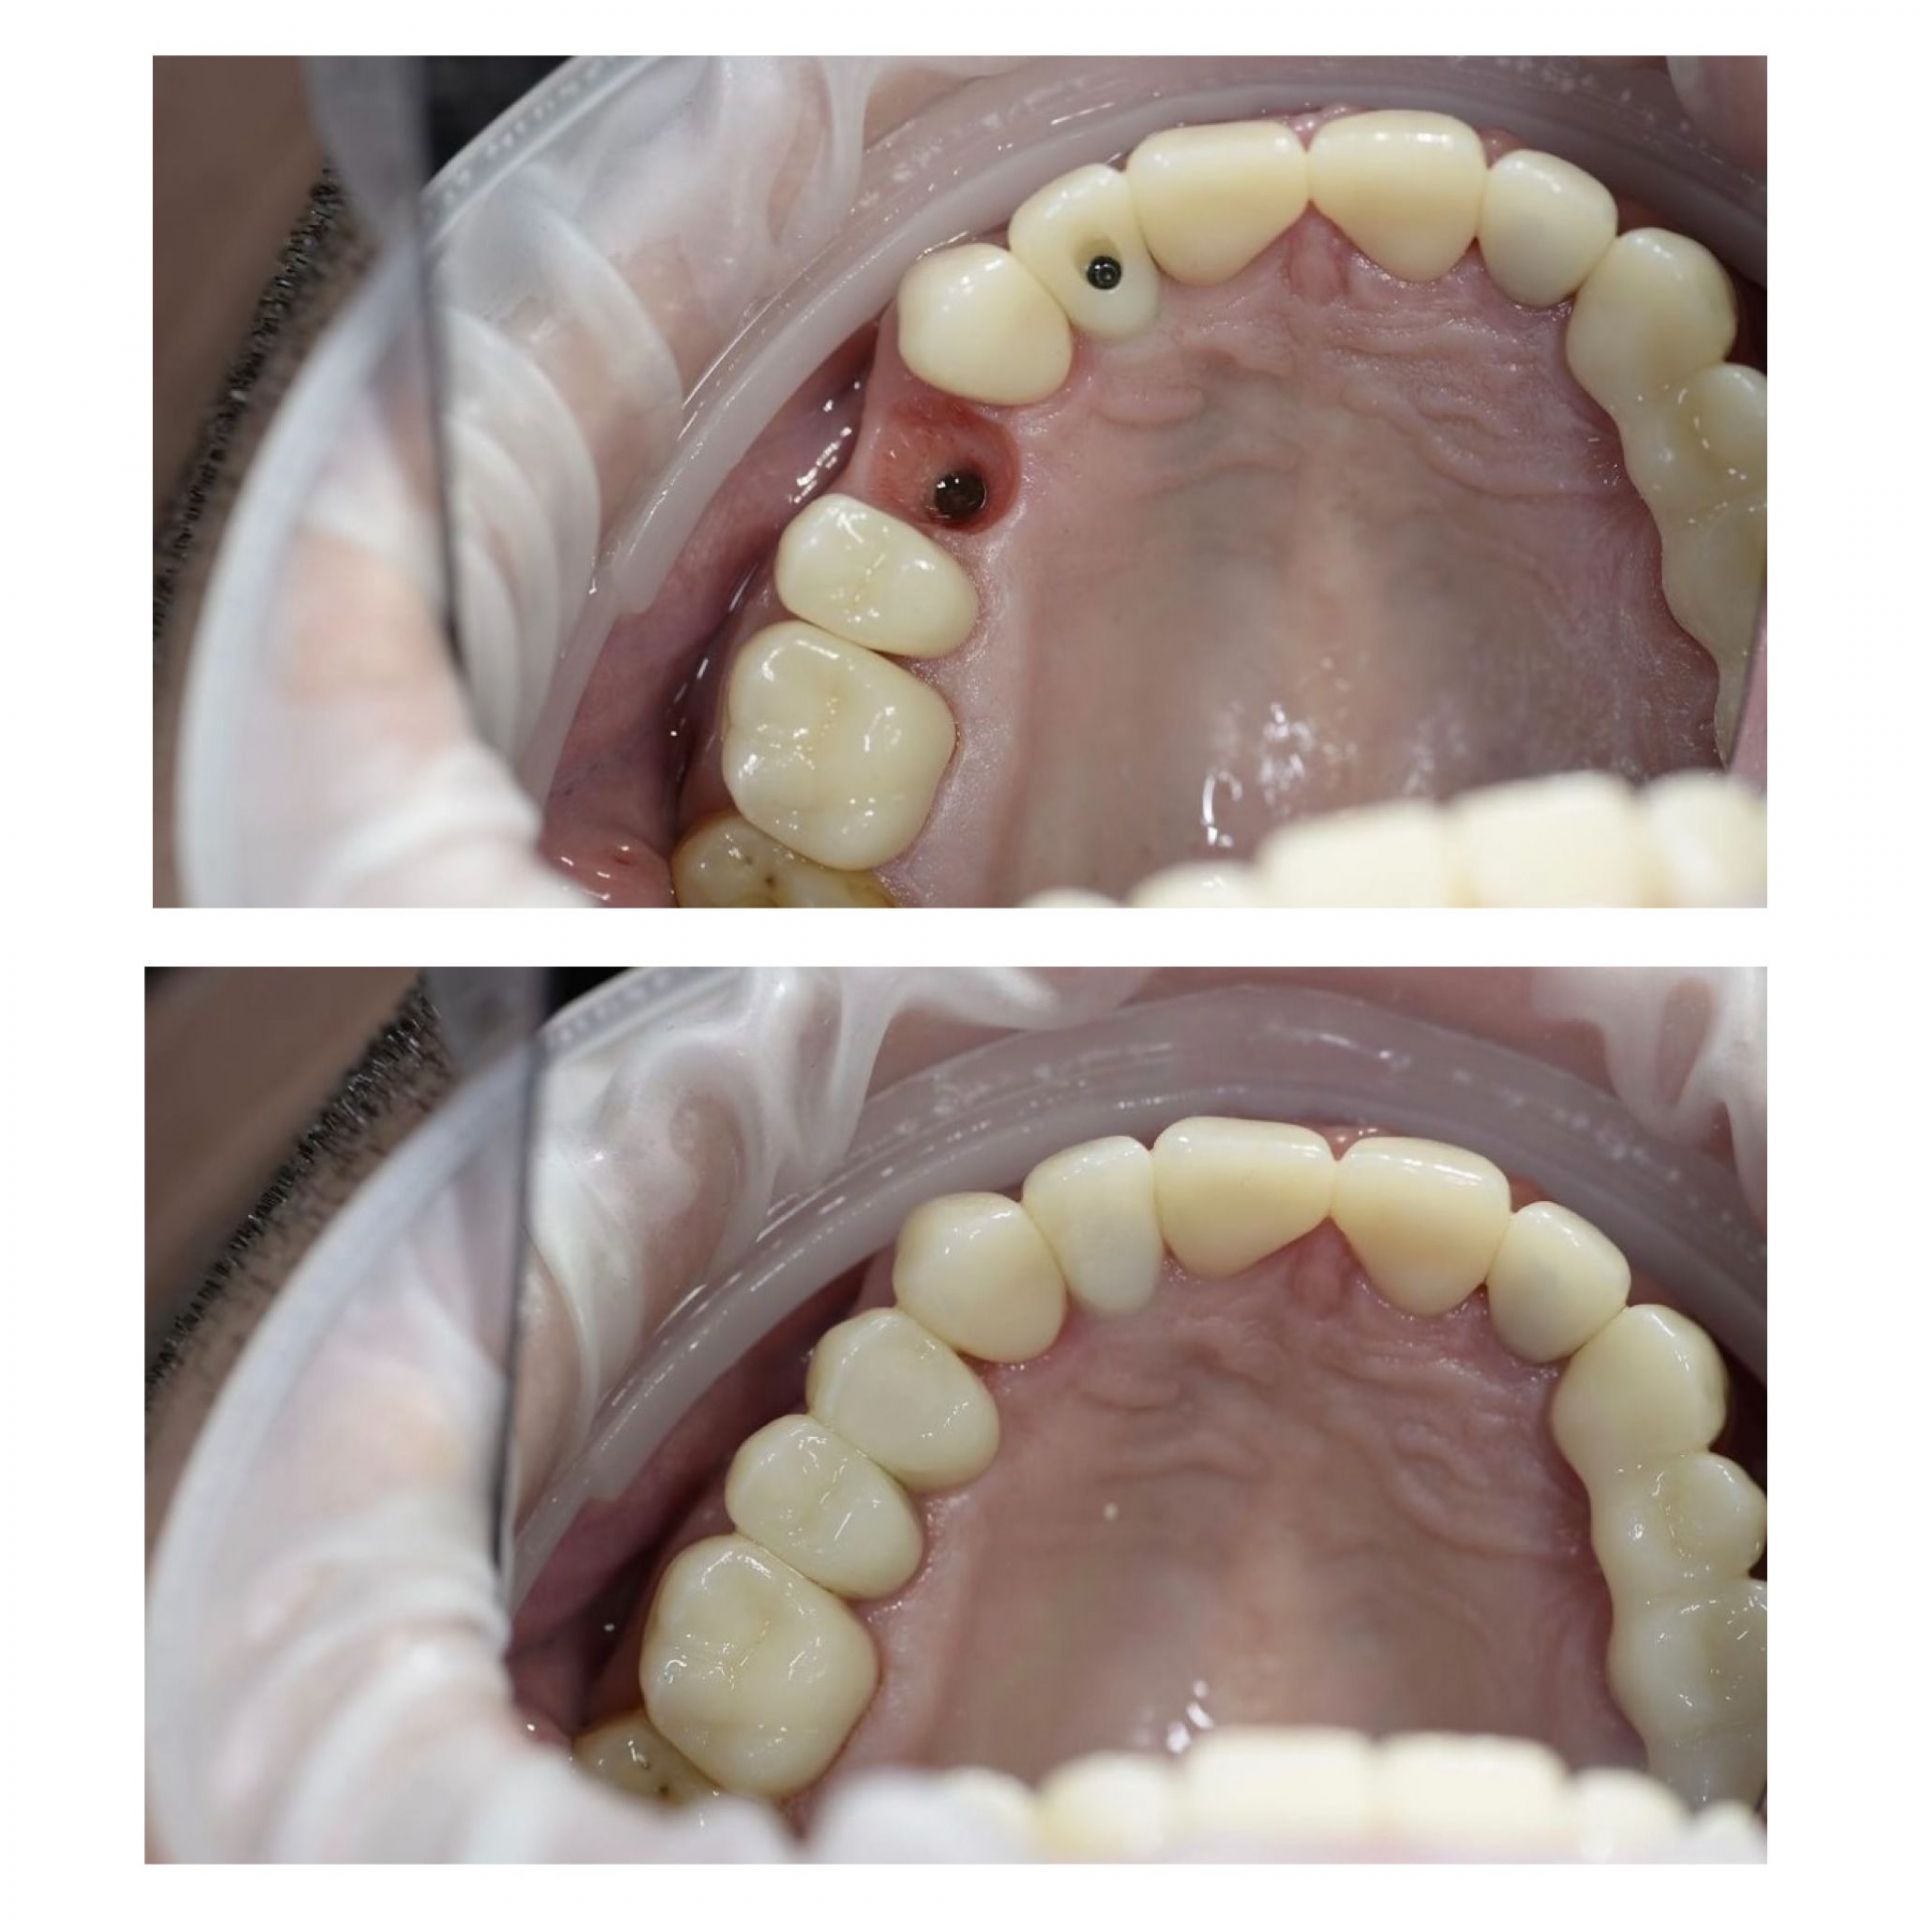

Імплант – це штучний корінь зуба, який виготовляється з титану. Він хірургічно вставляється в щелепну кістку, на ньому фіксується коронка, міст або протез. Імпланти відновлюють не лише естетику посмішки, але й функціональність зубів, даруючи Вам комфорт та впевненість.

Як відбувається сам процес імплантації в AsProDent:

- в місце відсутнього кореня вживлюється титановий імплант

- після приживлення імпланту, а це від 2-х до 6-ти місяців встановлюється формувач ясен

- пізніше встановлюється абатмент та тимчасова коронка

- завершальним етапом буде встановлення постійної коронки

Відсутість зубів призводить до негативних наслідків, починаючи від некрасивого естетичного вигляду, закінчуючи витонченням і деформацією щелепи. Тривала відсутність зуба призводить до зміщення сусідніх зубів, постійного скупчення їжі і, як наслідок, розвитку карієсу. Один з ефективних і сучасних способів усунення даної проблеми - це імплантація зубів.